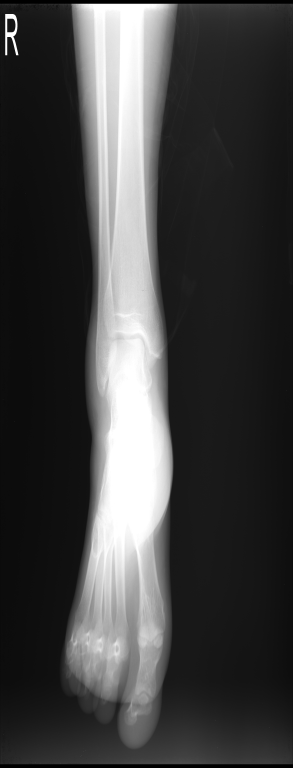

关节脱位:外伤性(常合并撕脱性骨折、韧带或软组织损伤。分为完全/半脱位);

非外伤性(先天性髋关节脱位)